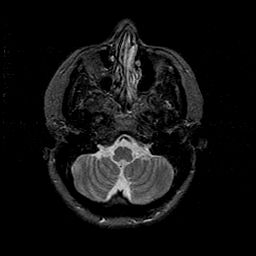

MR Study #1 -- Slice #12